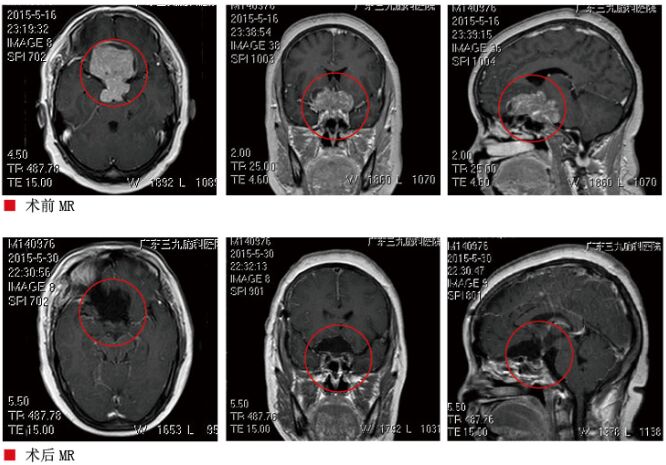

患者陈某,女,53岁,因多饮、多尿、视力下降4年,于2015年5月27日入院,6月17日出院,共住院21天。患者4年前开始出现多饮、多尿、视力下降,在当地医院检查CT发现“鞍区肿瘤”,为进一步治疗,就诊我院。入院查体:神志清楚,语言流利。视力左眼0.4,右眼10cm数指。视野粗测双颞侧偏盲。双侧瞳孔等大等圆,对光反射灵敏。眼球位置居中,无震颤,眼球活动正常。入院后查血糖高,生长激素低。视野检查提示左眼鼻下视野正常,鼻上、颞上下视野异常。右眼15cm数指,视野全向偏盲。入院后完善术前检查,头部MR提示鞍内、鞍上有一巨大占位病变,蝶鞍明显扩大,肿瘤最大径60mm×49mm×40mm。病灶包绕双侧大脑前动脉,考虑巨大垂体腺瘤。于6月1日在全麻下经右额外侧入路鞍区病变切除术,术中见肿瘤呈肉红色、质软、血运丰富,有包膜,予以分块切除肿瘤,术程顺利。术后病检结果:垂体腺瘤。术后右侧视力左眼0.6,右眼0.5,视野正常。多饮多尿减轻。术后电解质正常,血糖控制在正常范围内,术后头部MR示肿瘤全切,顺利出院。